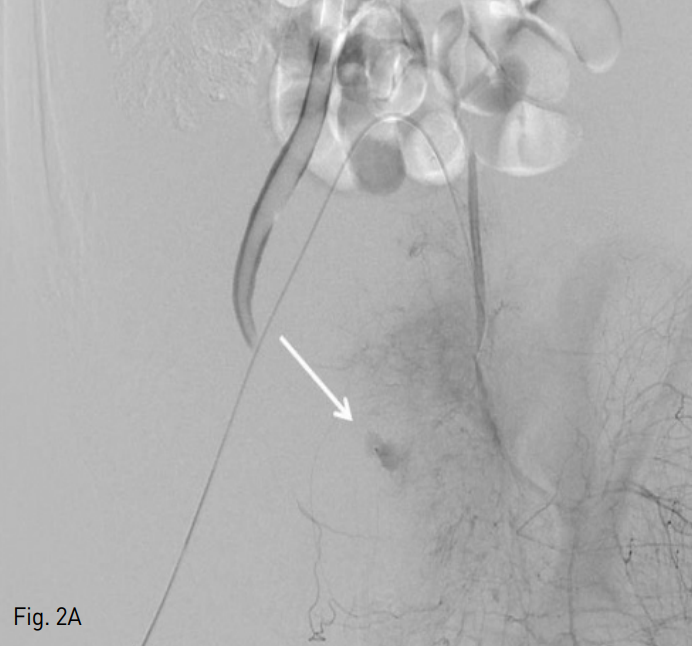

우측 총대퇴동맥을 천자한 후, 5 Fr sheath (Terumo, Tokyo, Japan)를 거치 시켰다. 이후 0.035 inch guide wire (Terumo, Tokyo, Japan)} 5 Fr pigtail catheter (Cook,Bloomington, IN,USA)를 이용하여 골반 동맥 조영술을 시행하였으며, 좌측 내장골동맥 분지에서 기시하는 분지에서 발생하고 있는 조영제의 유출 (Fig. 2A)을 확인하였다. 이어 5 Fr Cobra catheter (Cook, Bloomington, IN,USA)를 이용하여 좌측 내장골동맥을 선택한 후 시행한 조영술에서 동일 부위에 좌측 상방광동맥에서 기인한 조영제의 유출을 확인하였다. 2.2 Fr microcatheter (Progreat; Terumo, Tokyo, Japan)를 통해 좌측 상방광동맥을 초선택한 후 histoacryl glue (B. Braun, Melsungen AG, Germany)와 리피오돌 1 : 3 혼합액 1 cc를 이용하여 색전술을 시행하였다 (Fig. 2B). 색전술 후 다시 좌 내장골동맥 조영술에서 더 이상 조영제의 유출은 보이지 않았다 (Fig. 2C).

Fig. 2

A. Initial pelvic angiogram shows extravasation of contrast media (arrow in A) from the left superior vesical artery in left pelvic cavity.